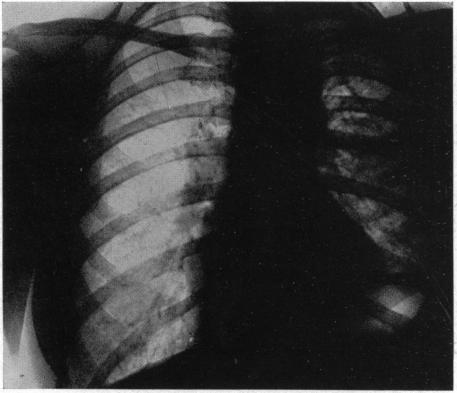

INTRATHORACIC DERMOIDS: WITH THE REPORT OF A CASE OF TOTAL EXTIRPATION AT ONE SITTING BY A NEW METHOD OF THORACOTOMY.

Ann Surg. 1928 Sep;88(3):607-32. doi: 10.1097/00000658-192809000-00030.